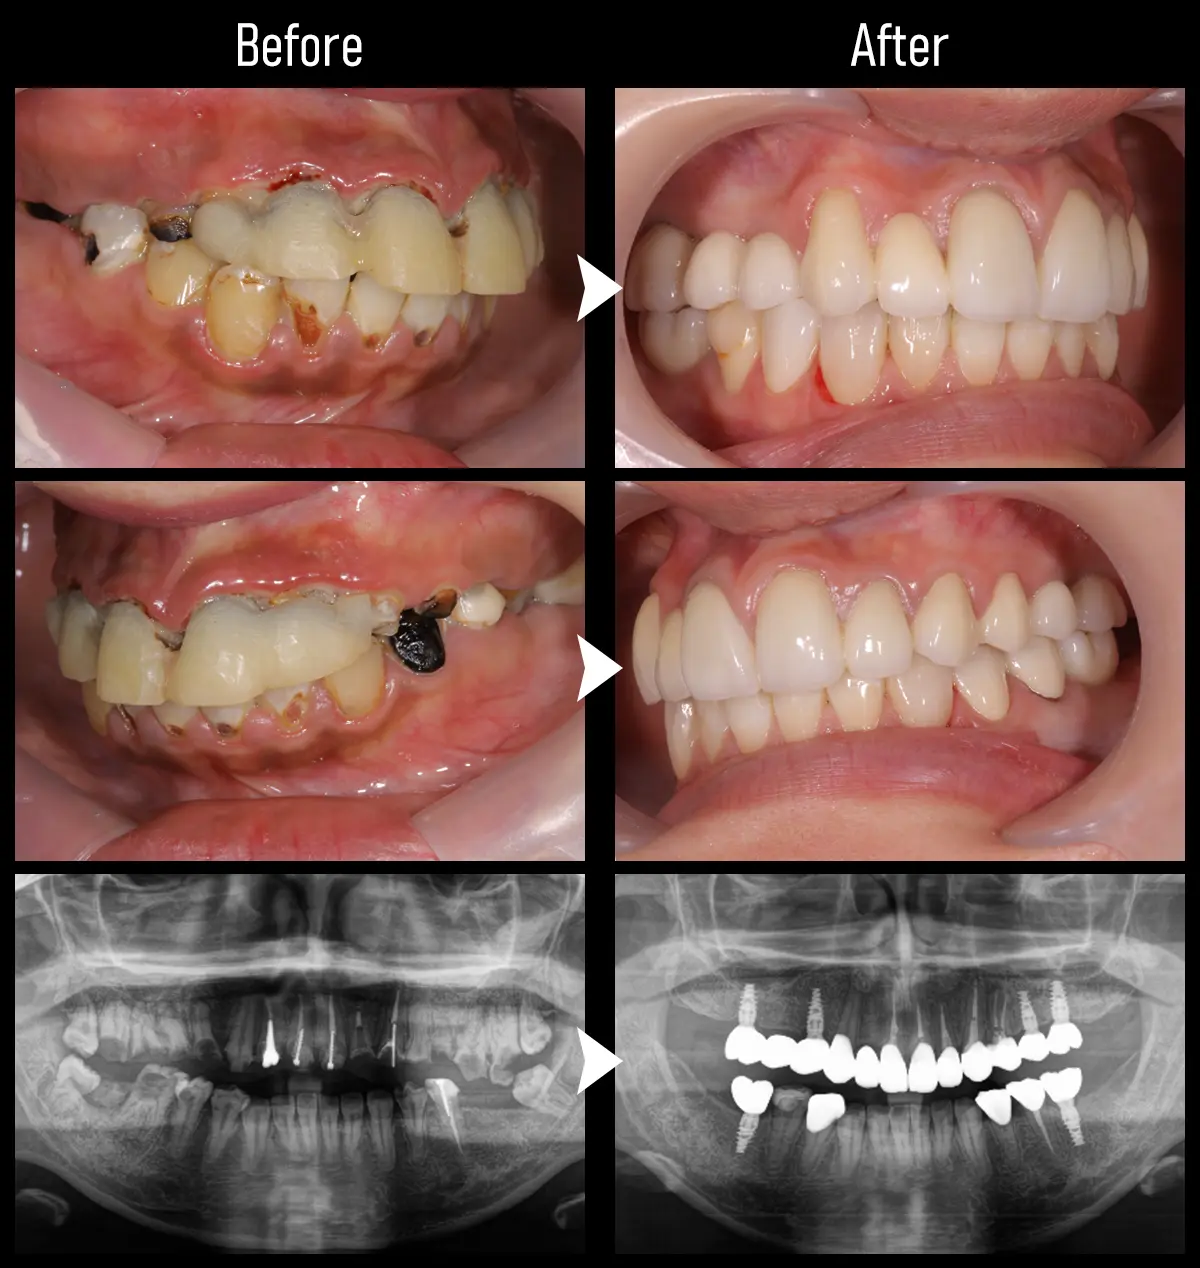

CASE:複数歯インプラント1

主訴 前歯が取れた

治療内容 前歯を含め、上顎にインプラント治療を5本と下顎左6番にインプラント治療を行い、下顎右の補綴治療も実施。

標準費用(自費) 635万円